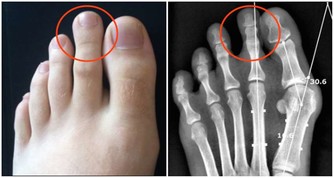

對一些人而言,長期使用某些藥物(如一些高血壓藥、治療關節炎或帕金森症的藥)會造成抑鬱症狀。